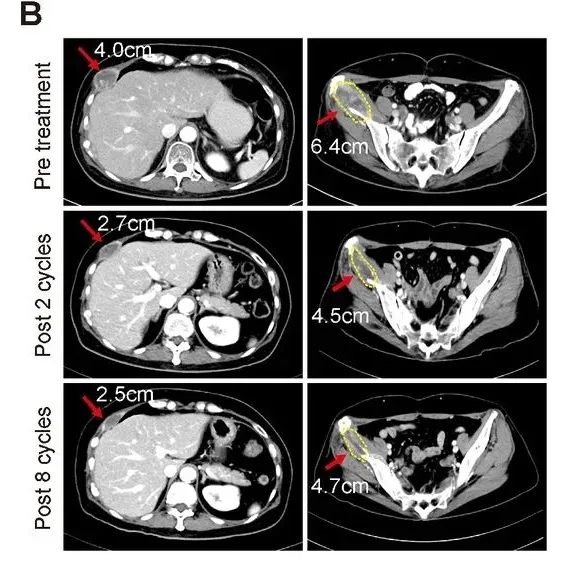

值得关注的是,其中1例55岁转移性激素受体阳性+HER2阳性乳腺癌患者还实现了部分缓解(PR):该患者既往已接受抗HER2治疗、激素疗法及多种化疗,经连续2个周期联合治疗后达PR,且这一状态持续至第8周期(详见下图)。此外,该患者的肿瘤标志物CA-153水平显著下降,治疗前为146.8,治疗第5周期降至75.4,治疗结束时仍稳定在76.6。

▲图源“AACR”,版权归原作者所有,如无意中侵犯了知识产权,请联系我们删除